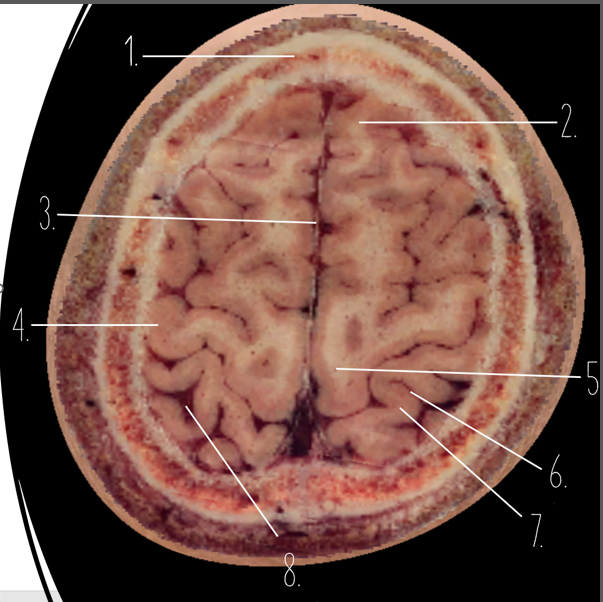

1

Frontal Bone

2

Frontal Lobe

3?

Falx Cerebri

4?

Gray Matter

5?

White Matter

6?

Sulcus

7?

Gyrus

8?

Fissure